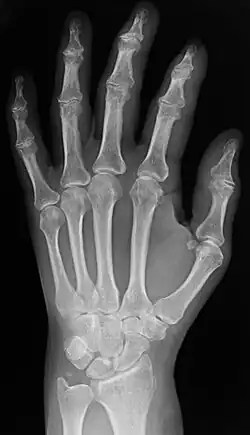

Radiography

Two forms of radiographic images are in use in medical imaging. Projection radiography and fluoroscopy, with the latter being useful for catheter guidance. These 2D techniques are still in wide use despite the advance of 3D tomography due to the low cost, high resolution, and depending on the application, lower radiation dosages with 2D technique. This imaging modality uses a wide beam of X-rays for image acquisition and is the first imaging technique available in modern medicine.

- Projectional radiographs, more commonly known as X-rays, are often used to determine the type and extent of a fracture as well as for detecting pathological changes in the lungs. With the use of radio-opaque contrast media, such as barium, they can also be used to visualize the structure of the stomach and intestines – this can help diagnose ulcers or certain types of colon cancer.